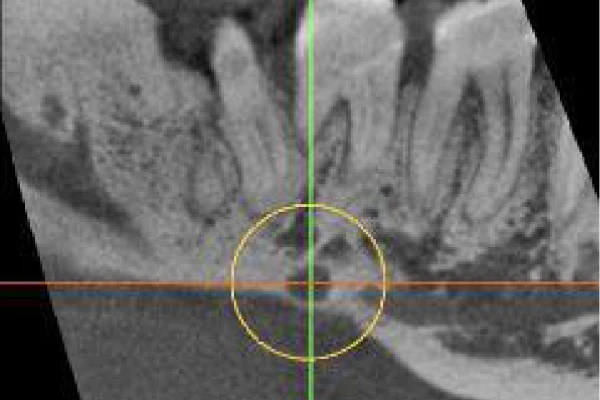

Ở mảng vỏ xương bên dưới răng cối số 7 hàm dưới là một lỗ được xác định rõ. Lỗ này rộng 4mm, mất mặt ngoài của mảng vỏ xương với khoảng tủy xương. Nó rất gần với ống thần kinh hàm dưới. Kèm theo là tình trạng viêm của nó có thể gây đau.

Lát cắt toàn cảnh của Răng cối hàm dưới từ số 6-8 và mặt cắt ngang của vùng LR6 cho thấy ống tủy, chiều rộng dây chằng nha chu bình thường và lớp màng cứng. Cũng có thể thấy không gian nang mở rộng liên quan đến LR8.